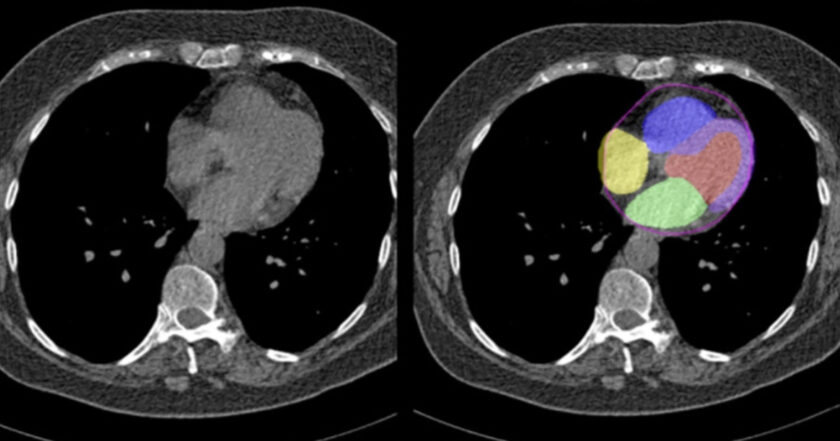

La inteligencia artificial identifica el riesgo cardiovascular en mamografías

Según información de Medscape, la inteligencia artificial (IA) es capaz de identificar el riesgo cardiovascular a través del análisis de mamografías.